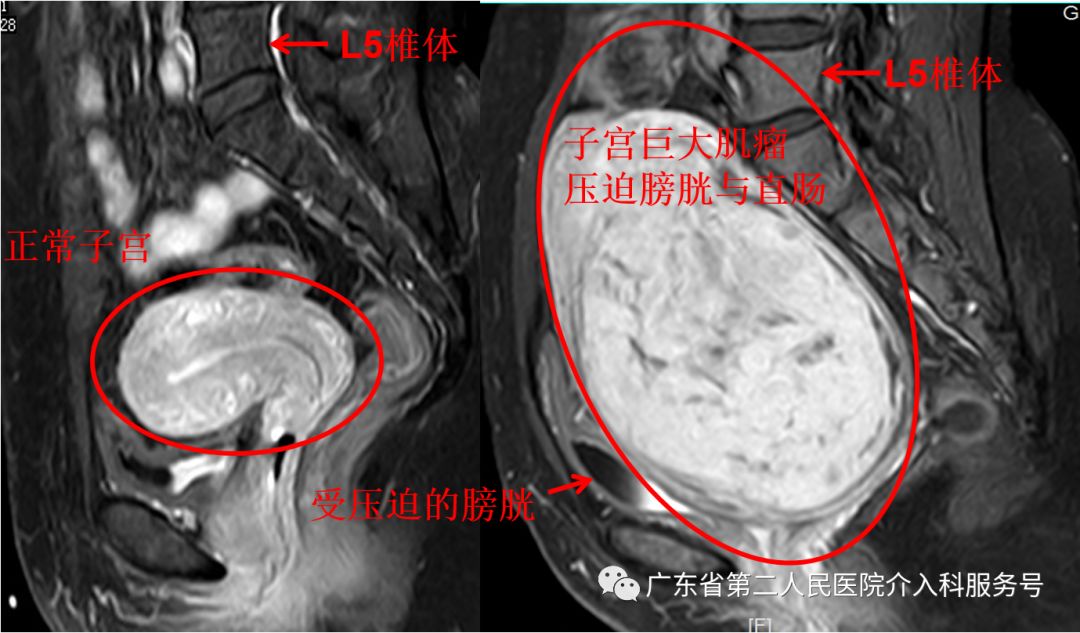

下图为王女士的磁共振检查:宫颈管巨大子宫肌瘤(国际妇产科联盟(FIGO)子宫肌瘤Ⅷ型,大小约13m*11cm*10cm)

下图为正常的子宫与王女士巨大子宫肌瘤磁共振对比图